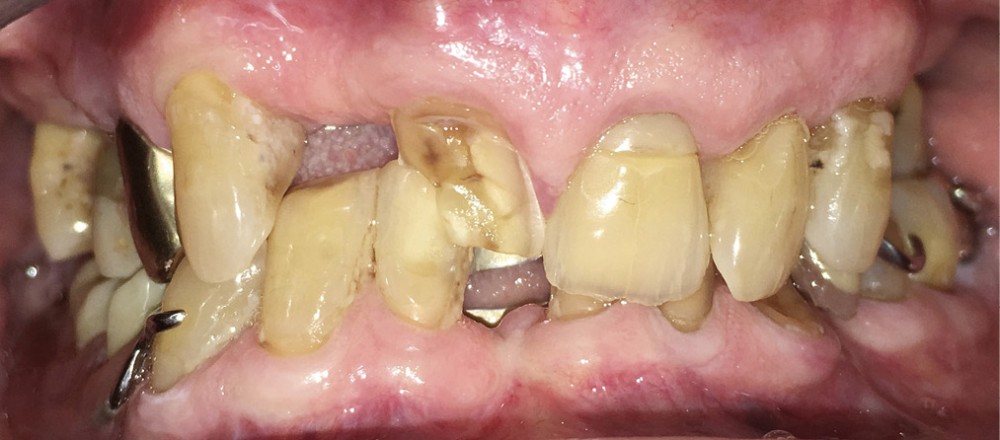

En 2017, l’examen clinique de la face révèle un menton projeté vers l’avant et un léger affaissement des commissures labiales (fig. 2a, b).

Le maxillaire présente un édentement de classe III subdivision 2 de Kennedy-Applegate (K-A). La 12 est absente et la 11 fracturée. 24-25-26 ont été extraites depuis longtemps (fig. 3a). 15 et 17 sont dépulpées et restaurées avec des composites anciens mais non infiltrés.

À la mandibule, une prothèse partielle à armature métallique conçue selon les critères ayant fait l’objet d’un large consensus, compense un édentement de classe II, subdivision 3…